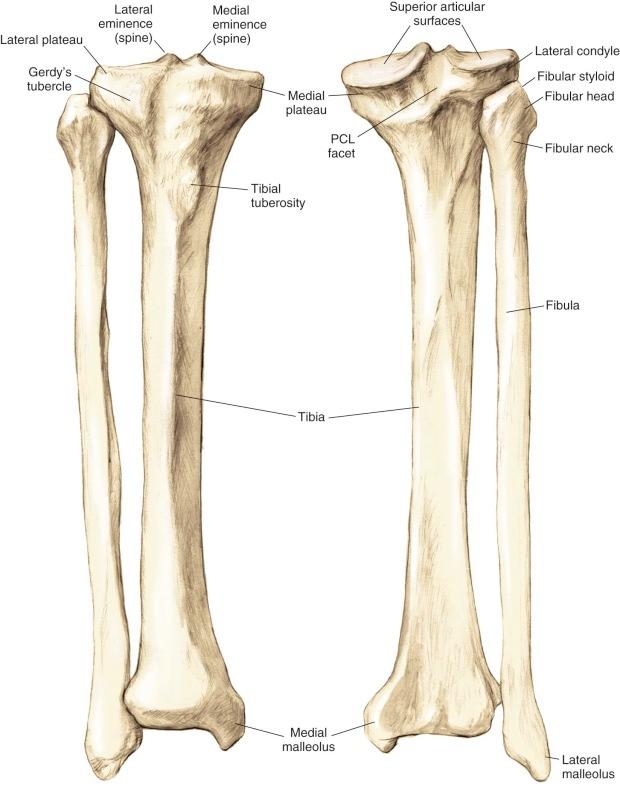

Proximal Tibia ( Fig. 7-2 )

• The tibia is the second longest bone in the body

• The plateau areas match the corresponding femoral condyle

• The medial tibial plateau is broad and concave

• The lateral tibial plateau is smaller and convex

• The tibial eminences (spines) define the borders of the cruciate ligament insertions

• The ACL lies between the eminences

• The PCL lies within the PCL facet, adjacent to the posterior aspects of the medial and lateral tibial plateaus; in addition, its distal fibers attach at the posterior tibial drop-off, which radiographically is known as the “champagne glass drop-off” of the tibia

• The tubercles serve as attachments for tendons

• The tibial tubercle (or tuberosity) serves as the patellar tendon attachment

• Gerdy's tubercle serves as the iliotibial band attachment

FIGURE 7-2, Bony architecture of the proximal tibia. PCL, Posterior cruciate ligament.